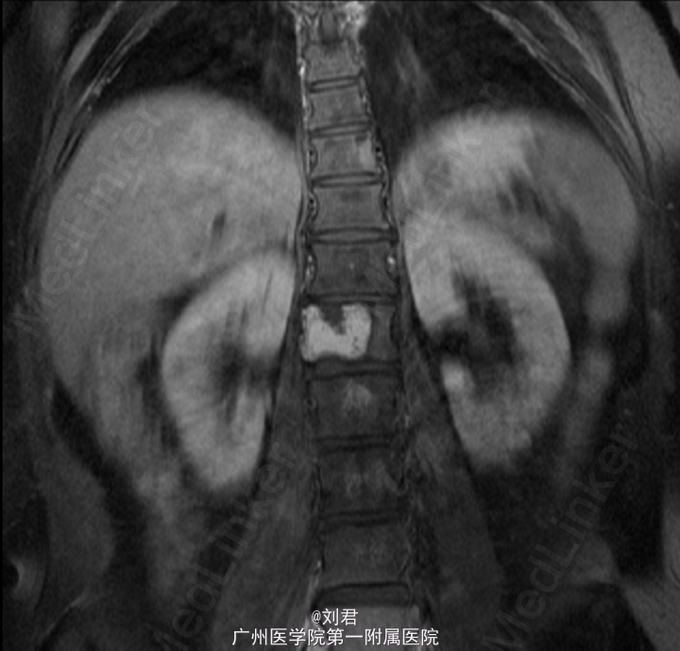

患者,女,52岁,因“右后髂部疼痛1年余。”入院。 患者1年余前出现右后髂部疼痛,疼痛程度较轻,不伴有下肢放射痛、下肢活动受限等不适.

脊椎外观无畸形。胸腰椎无明显压痛、叩击痛。双下肢直腿抬高试验阴性,双下肢感觉无异常,肌力、肌张力正常。腰椎椎间盘扫描:腰1椎体肿瘤,考虑椎体血管瘤可能。建议增强MRI扫描观察。腰椎磁共振增强扫描:腰1、2肿瘤,倾向于恶性肿瘤,转移?骨髓瘤?

初步诊断:腰椎肿瘤. 手术指征明确,行腹主动脉造影+腰椎动脉超选造影+胸12、腰1、2动脉栓塞术,后行腰椎肿瘤后路肿瘤切除、椎管减压、内固定术。

术后病理:(腰1椎体)血管瘤。术后予抗感染、止痛等治疗。患者术后恢复可,复查腰椎X片示内固定位置可.